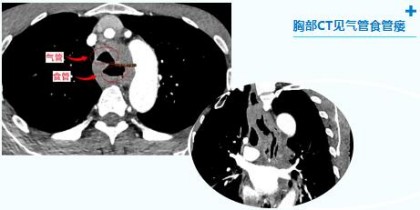

经胸部CT等检查后发现:气管食管瘘、肺部感染。就好比气管和食管间穿了个“洞”,病情危急!胃内容物通过瘘口反流至肺部造成严重的吸入性肺炎,如不把误吸的胃内容物和浓痰吸出,气管食管瘘不予以封堵,肺部感染无法控制!

胸部CT见气管食管瘘